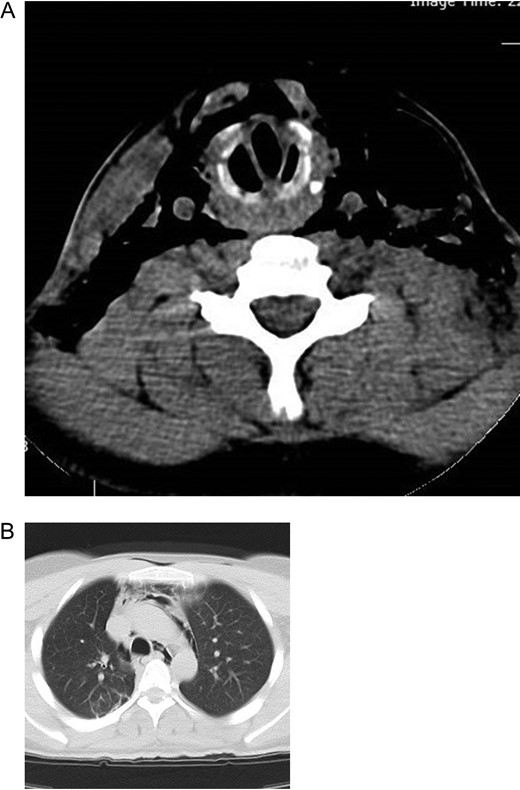

A 25-year-old man arrived in the emergency room 8 h after a motor accident in which a rope was wrapped around his neck. Initial pulse oximetry saturation (SpO2) was 94%. The vital signs included a blood pressure of 122/80 mmHg, a heart rate of 98 beats/min, a respiratory rate of 23 breaths/min, and an axillary temperature of 36.2°C. Because of the good general and respiratory condition of the patient on admission, the pathognomonic signs of laryngeal injury were not noticed. Patient had skin contusion and moderate crepitus on his neck area (Fig. 1). His phonation was normal without dyspnea, cough, hemoptysis or hoarseness. Pneumomediastinum and subcutaneous emphysema were noted on a supine chest radiograph (Fig. 2). Computed tomographic (CT) scan of the neck and chest revealed pneumomediastinum, subcutaneous emphysema in the neck and distortion of laryngotracheal framework (Fig. 3). Flexible bronchoscopy showed cricotracheal transection with normal movement of true vocal cord. At the same setting, endotracheal tube was advanced distal to the transection site under bronchoscopic guide (Video). Neck exploration demonstrated complete cricotracheal separation (Fig. 4). The area was debrided and primary cricotracheal end-to-end anastomosis was performed. The patient was extubated 2 days after the surgery. Fiberoptic bronchoscopy on Days 20 and 90 showed that the tracheal injury healed completely with no apparent proliferation of granulation tissue.

(A) CT image of the neck showing subcutaneous emphysema and larygotracheal framework distortion. (B) CT image of the chest showing pneumomediastinum.